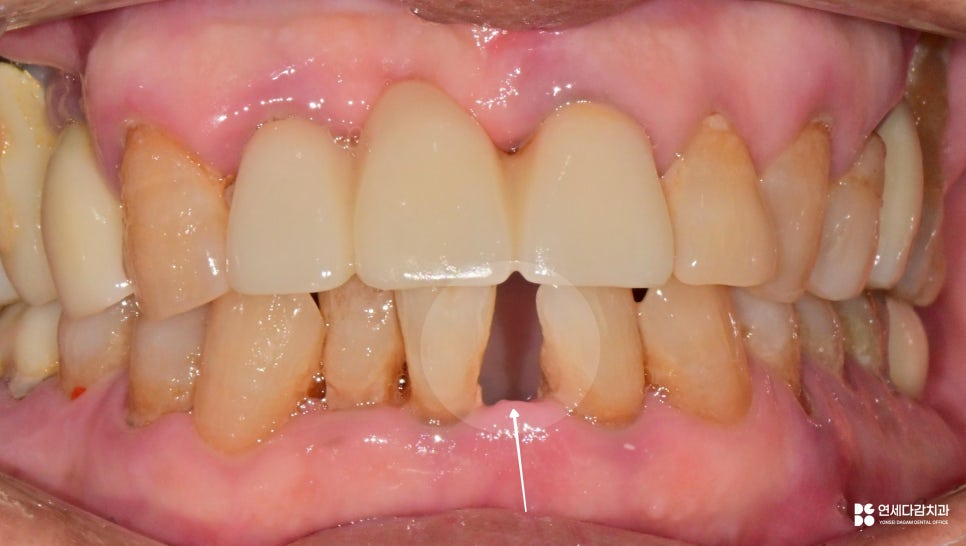

그럼, 어떤 상황으로 이어지는지

예시 자료로 살펴보도록 하겠습니다.

심한 경우 외상이나 사고가 없더라도

자연스럽게 탈락하는 문제로 이어집니다.

2025.12.14 정말 정성스럽게 우유에 포장해서 온 아래 앞니

우선 탈락한 치아는 그대로 보존해야 되며,

우유나 생리식염수에 담가주어 건조되지 않게 하여

함께 내원을 하는 것이 좋습니다.

다만, 치조골이 이미 소실된 케이스에서는

재식이 불가능한 경우가 많습니다.

이러한 변화를 방지하기 위한 방법 중 하나가

바로 '잠간 고정술'입니다.

이는 탈락한 부위 주변 환경을 고려해

간단한 레진 등의 재료를 이용하여

임시로 메워주는 방법으로 진행됩니다.

다만, 개롱역 치과 에서 보여드리는 것과 같은

발치된 치아를 이용한 방식 같은 경우

일반적인 방법과는 다릅니다.

보통 흔들리는 곳과 그렇지 않은 치아를

서로 접착하면 유지력을 잃게 될 수 있습니다.

이 경우 환자분께서 발거치아를

꼭 다시 붙이시길 원하셨습니다.

환자분이 충분한 설명을 이해하고

사용에 제한을 두는 조건으로 처치를 원할 경우

예외적으로 시행되기도 합니다.